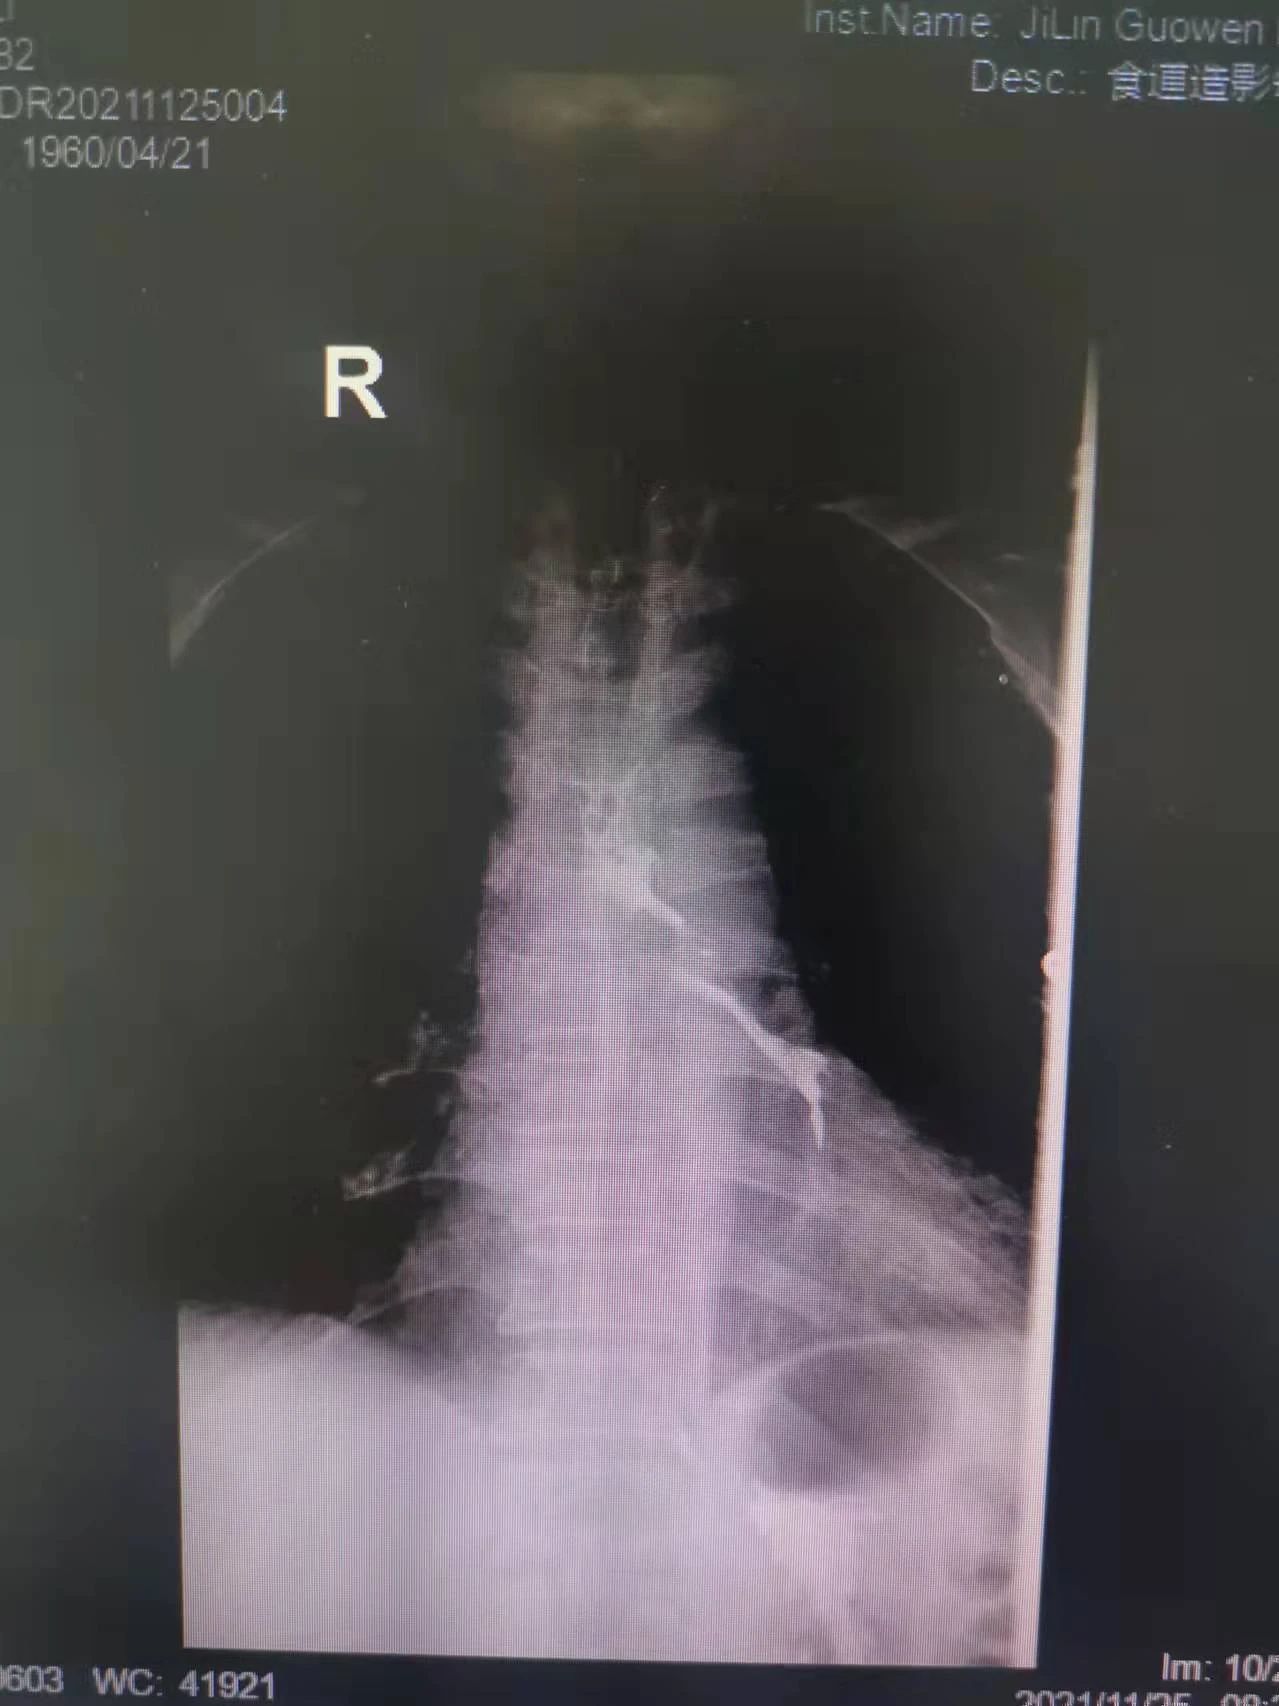

“大夫,我能喝點(diǎn)水么,我嗓子熱”今年61歲的付大爺患有食管惡性腫瘤。起初付大爺進(jìn)食時(shí)吞咽困難,每日進(jìn)食量極少,后隨著疾病的發(fā)展,付大爺進(jìn)食后伴隨劇烈嗆咳,經(jīng)系統(tǒng)檢查后,明確診斷為食管氣管瘺。為防止食物進(jìn)入氣管加重感染,付大爺聽(tīng)從了醫(yī)生禁食水的意見(jiàn)。現(xiàn)如今,付大爺每日不光承受著癌癥所帶來(lái)的疼痛,還要承受著禁食水后仿佛置身于沙漠般的口干舌燥。這段時(shí)間里,喝一口水這么一個(gè)小小的愿望對(duì)于他來(lái)說(shuō)都已成奢求!有著正常食欲卻無(wú)法進(jìn)食,可以想象對(duì)于人的生理及心理帶來(lái)多么大的創(chuàng)傷。家屬眼見(jiàn)付大爺痛苦不已,也是焦急萬(wàn)分。

在這種情況下,我院介入二科侯主任決定通過(guò)介入治療中的食管支架植入來(lái)幫助患者實(shí)現(xiàn)這個(gè)愿望。手術(shù)當(dāng)日,侯主任在機(jī)器的幫助下,將一根細(xì)細(xì)的導(dǎo)絲穿過(guò)腫瘤到達(dá)付大爺胃部,然后再沿著導(dǎo)絲,把壓縮好的支架放在腫瘤里面。通過(guò)后撤導(dǎo)管,把壓縮的支架打開,支架把腫瘤撐開,讓食管不再堵塞。有了支架的支撐,付大爺就可以自由地吃東西了,哪怕食管和氣管有溝通,因?yàn)橹Ъ芨采w了腫瘤,通道堵住了,吃的東西也不會(huì)吸到肺內(nèi)造成感染。這時(shí)痛痛快快地吃上一頓,也不再是奢望!

手術(shù)很順利,付大爺也在術(shù)后第2天喝到了自己日思夜想的清水,露出了久違的笑容。從某種意義上講,介入食管支架置入術(shù)的成功實(shí)施,付大爺不能進(jìn)食的病已經(jīng)“治好”了,雖然從生理角度來(lái)說(shuō),付大爺可以通過(guò)終生使用腸內(nèi)營(yíng)養(yǎng)來(lái)維持生存,但我們所做的是致力于給予患者更好的生存體驗(yàn),或者說(shuō)是尊嚴(yán)。銘記并保持一名醫(yī)者的初心,我們要做的正如那句著名的墓志銘所說(shuō):有時(shí)去治愈,常常去幫助,總是去安慰。